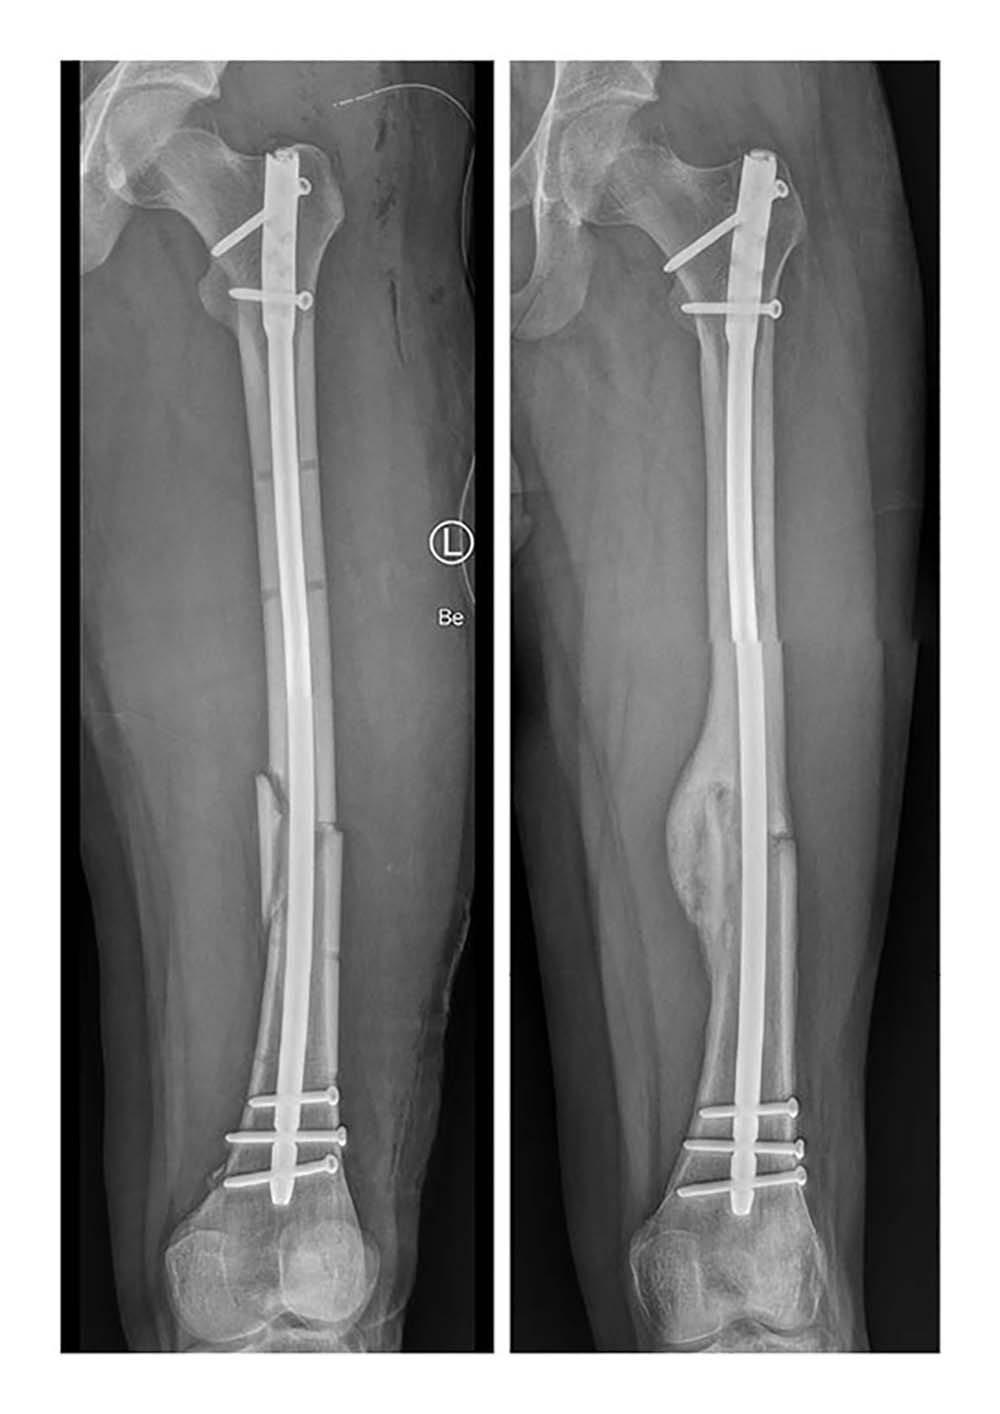

Für die Simulation wurden die klinischen Daten von 36 Patient*innen rückblickend analysiert. Diese hatten sich einen Schaftbruch des Oberschenkelknochens zugezogen, der durch die Implantation von Marknägeln versorgt worden war. Mithilfe von postoperativen Daten konnte die Computersimulation das Heilungsergebnis von 30 Fällen korrekt vorhersagen. „Bisherige Studien zum Ulmer Frakturheilungsmodell basierten auf Daten aus Tierversuchen oder aus Versuchen unter Laborbedingungen. Die Kooperation mit dem UKU hat es uns nun ermöglicht, das Heilungsmodell erstmalig mit klinischen Daten zu testen. So konnten wir den Prototypen des Softwaretools weiterentwickeln“, sagt Dr. Lucas Engelhardt von OSORA. „Das Heilungsmodell ist nicht nur in der Lage, Informationen zu erfolgreichen Heilungsverläufen zu generieren. Es wird ebenso zukünftig möglich sein, das Risiko für Komplikationen bis hin zu Pseudoarthrosen – also knöchernen Fehlheilungen – zu kalkulieren“, ergänzt Dr. Frank Niemeyer, ebenfalls von OSORA. Unter Berücksichtigung von patientenindividuellen Parametern, wie Größe und Gewicht, und Begleiterkrankungen, wie Osteoporose oder Adipositas, können dann Behandlungswege für jeden Patienten und jede Patientin individuell erstellt werden. Die Simulation unterstützt so die ärztliche Expertise durch Informationen zur Belastungsfähigkeit des Knochens während der Heilung.

Lediglich in sechs Fällen – von denen zwei Knochenbrüche geheilt und vier nicht geheilt waren – war die Prognose der Computersimulation nicht korrekt. „Jeder Patient heilt anders, jede Fraktur hat ihre Besonderheiten. Wir können aus den Daten ableiten, warum die Simulation in diesen Fällen nicht den realen Frakturheilungsverlauf abbildet, um neben der Biomechanik weitere Einflüsse auf das Knochenwachstum im Modell mit zu berücksichtigen. Diese Informationen sind für die weitere Entwicklung unserer Softwareplattform von größter Bedeutung, um die Präzision der Vorhersage kontinuierlich zu erhöhen“, erklärt Dr. Lucas Engelhardt.

„Die chirurgische Versorgung von Frakturen durch Osteosynthese – also die operative Verbindung von zwei oder mehr Knochen oder Knochenfragmenten – ist ein elementarer Baustein in der Therapie unserer Patienten. Je früher Einflussfaktoren erkannt werden, die den Heilungserfolg gefährden, desto mehr Spielraum hat der behandelnde Arzt für Anpassungen des Therapieplans. Mit der biomechanischen Analyse und Simulation des Heilungsverlaufs kann zukünftig ein weiteres Hilfsmittel die Behandlungsmöglichkeiten ergänzen und Ärztinnen und Ärzte unterstützen“, so PD. Dr. med. Konrad Schütze, Oberarzt an der Klinik für Unfall-, Hand-, Plastische und Wiederherstellungschirurgie.